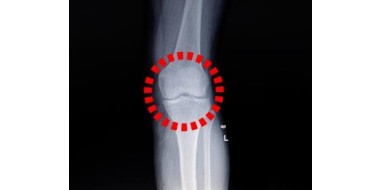

Een voetbalknie

Nooit een schot gelost en toch een voetbalknie, dat moet je als huisarts even uitleggen. Dat vervolgens een afwachtend beleid het beste is, zoals de NHG-Standaard Traumatische knieklachten adviseert, vereist mogelijk nog meer uitleg aan de altijd kritische patiënt. Bij gebrek aan goed opgezet…